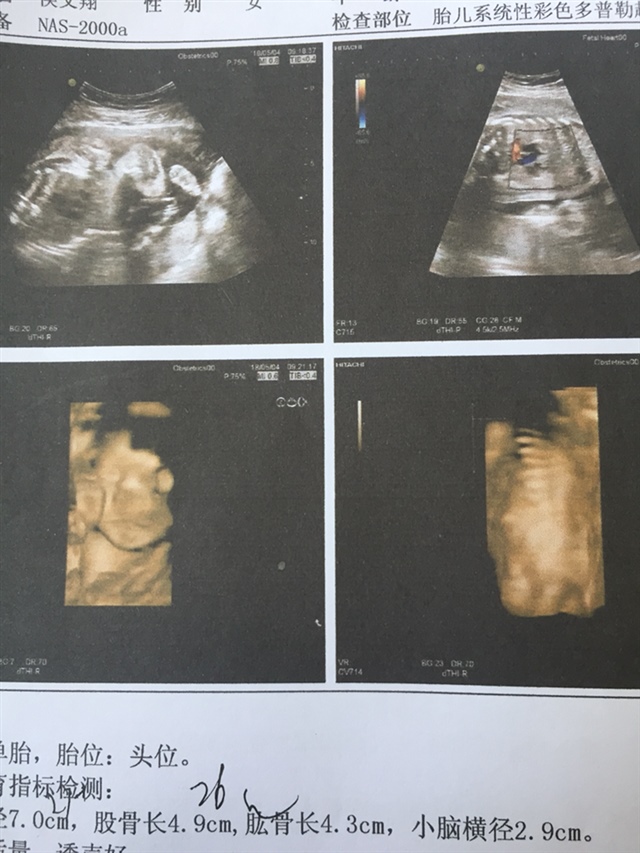

产前检查 B超